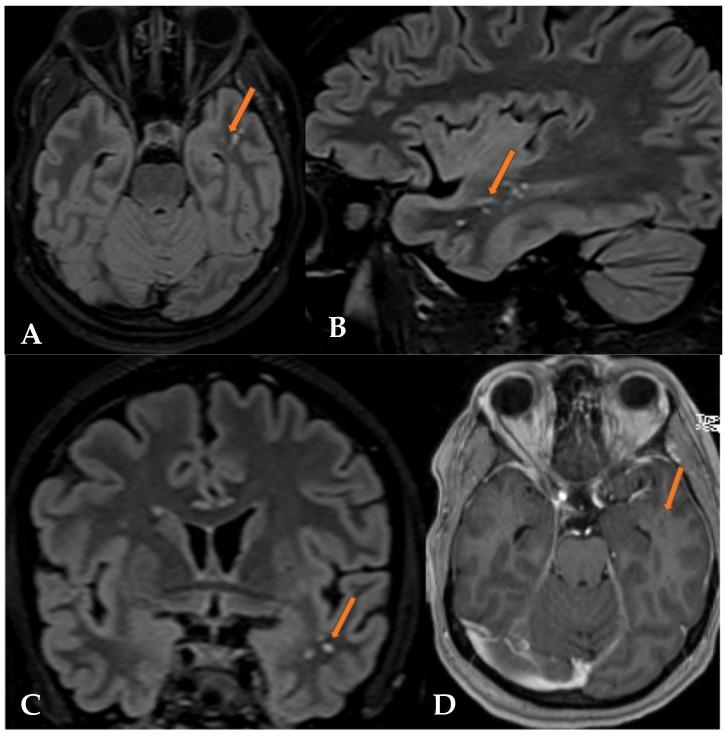

Multinodular Vacuolating Neuronal Tumors (MVNTs) are mixed glial-neuronal brain lesions classified as World Health Organization (WHO) CNS grade 1 tumors, often associated with long-term epilepsy. First described by Huse et al. in 2013 and included in the WHO CNS classification in 2016, MVNTs present a range of clinical manifestations, from symptomatic to asymptomatic. They typically affect young to middle-aged adults and exhibit diverse presentations. Radiologically, MVNTs are usually supratentorial, frequently located in the temporal lobe but also observed in the frontal and parietal lobes. MRI is essential for diagnosis, revealing multiple coalescing subcortical or cortical nodules with hyperintense signals on T2-weighted/FLAIR sequences, often without peripheral edema or mass effects. This paper presents two cases: one symptomatic MVNT with significant clinical manifestations, and the other documenting an incidental finding of MVNT in an asymptomatic patient. One case shows typical temporal lobe localization, while the other highlights a rare frontal lobe localization, with clear radiological findings on T2/FLAIR sequences. These cases illustrate the varied clinical presentations of MVNTs and emphasize MRI's critical role in diagnosis and management. Asymptomatic cases often require conservative management, stressing the avoidance of unnecessary invasive procedures and the importance of regular monitoring.

多结节空泡状神经元肿瘤(MVNTs)是一种神经胶质-神经元混合性脑病变,被归类为世界卫生组织(WHO)中枢神经系统1级肿瘤,常与长期癫痫相关。MVNTs于2013年由胡斯等人首次描述,并于2016年被纳入WHO中枢神经系统分类,其临床表现多样,从有症状到无症状。它们通常影响年轻至中年成年人,表现形式多样。在影像学上,MVNTs通常位于幕上,常位于颞叶,但也可见于额叶和顶叶。磁共振成像(MRI)对诊断至关重要,显示在T2加权/液体衰减反转恢复(FLAIR)序列上有多个融合的皮质下或皮质结节,信号增强,通常无周围水肿或占位效应。本文介绍了两例病例:一例是有明显临床表现的有症状MVNT,另一例记录了在一名无症状患者中偶然发现的MVNT。一例显示典型的颞叶定位,另一例突出了罕见的额叶定位,在T2/FLAIR序列上有明确的影像学表现。这些病例说明了MVNTs的不同临床表现,并强调了MRI在诊断和管理中的关键作用。无症状病例通常需要保守治疗,强调避免不必要的侵入性手术以及定期监测的重要性。